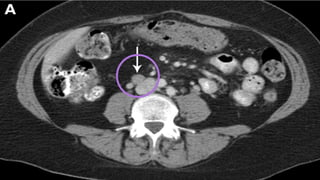

IMAGING STUDIES….. EAU

COMPUTED TOMOGRAPHY

UROGRAPHY ….. ADVANTAGES

Computed tomography (CT) urography is used

to:

 Detect papillary tumours in the urinary tract,

which can be seen as filling defects

 Hydronephrosis.

 Status of lymph nodes.

 Neighbouring organs.

IMAGING STUDIES….. EAU COMPUTEDTOMOGRAPHY UROGRAPHY ….. ADVANTAGES Computed tomography (CT) urography is used to:  Detect papillary tumours in the urinary tract, which can be seen as filling defects  Hydronephrosis.  Status of lymph nodes.  Neighbouring organs.